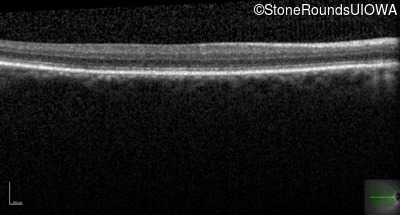

Infrared Fundus Photograph - Left - 20/125 -1 sc

Exemplar